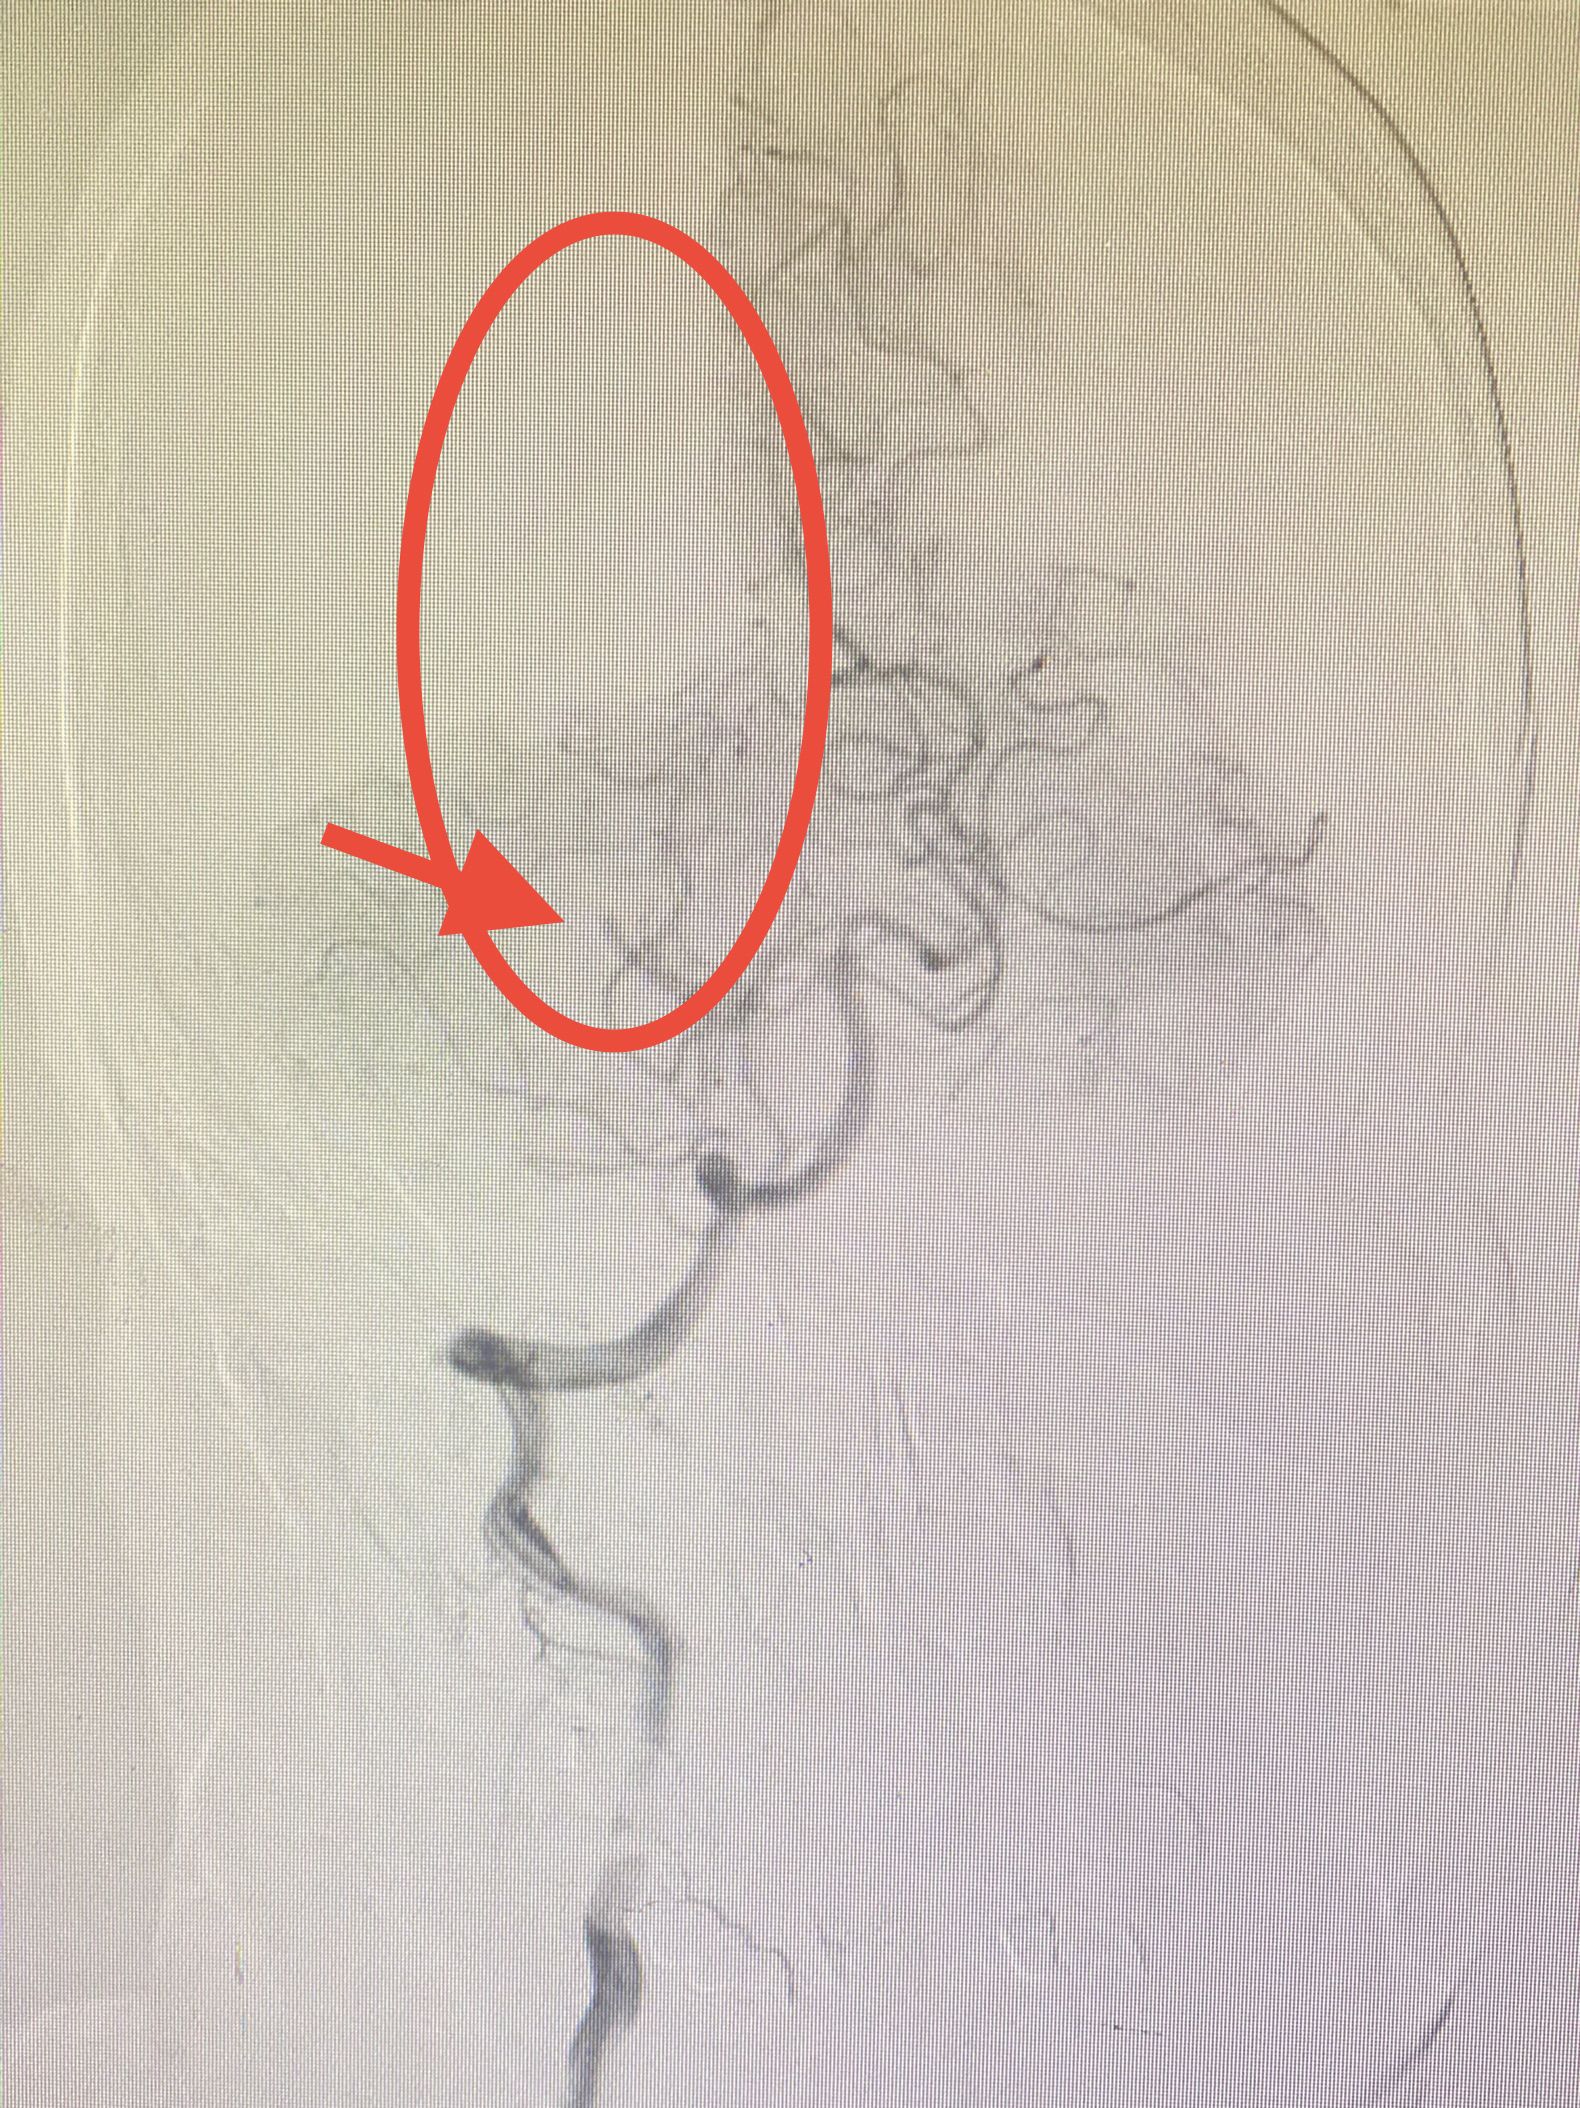

神经内科介入组立即开通绿色通道,5分钟完成造影检查,造影见:右侧大脑后动脉闭塞,闭塞残端杯口状,局部可见血栓影,考虑血栓栓塞。(图3)

图3:右侧大脑后动脉闭塞(红箭),远端无血流(红圈)